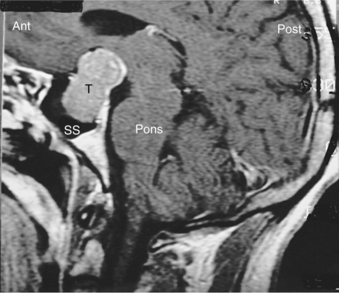

Pathogenesis.: With recent advances in molecular techniques, genetic abnormalities associated with pitu- itary tumors are becoming clearer. The great majority of pituitary adenomas are monoclonal in origin, suggesting that most arise from a single somatic cell. Additional molecular abnormalities present in aggressive pituitary adenomas and include mutations of the RAS oncogene and overexpression of the c-MYC oncogene, which suggests that these genetic events are linked to disease progression.67 Small lesions of the pituitary gland called microadenomas are less than 10 mm in diameter, and may be asymptomatic. Most grow in the front two thirds of the pituitary gland. Larger tumors, or macroadenomas, may compress the adjacent normal pituitary gland. Fig. 30-12 shows a pituitary tumor extension down into the sphenoid sinus. Extension of the tumor above the sella turcica compresses the optic chiasm.

Overview.: Pituitary adenomas are benign tumors derived from cells of the anterior portion of the pituitary gland. The pituitary gland, located at the base of the brain, sits in the sella turcica, the saddle-shaped transverse depression on the superior surface of the body of the sphenoid bone. Fig. 30-11 gives the anatomic relations of the pituitary gland, optic chiasm, and surrounding parasellar structures. Although pituitary adenomas are the most common of the pituitary tumors, infrequently other types of pituitary tumors may occur in the location of the pituitary gland and may be primary or metastatic. See also the section Pituitary Gland in Chapter 11.

Clinical Manifestations.: In the majority of pituitary tumors, the release of excess pituitary hormones or pituitary insufficiency results in dramatic and unique clinical syndromes. Galactorrhea and amenorrhea, gigantism and acromegaly, and the symptoms of Cushing’s disease (hypertension, facial and truncal obesity, osteoporosis, muscle weakness, menstrual abnormalities, and female hirsutism) are among the hormonal symptoms. Pituitary insufficiency, or hypopituitarism, can lead to symptoms such as fatigue, weakness, and hypogonadism. A second pattern of presentation consists of regression of secondary sexual characteristics and hypothyroidism. The third pattern of presentation is one of neurologic findings, including headache, bitemporal visual loss, and ocular palsy. Fig. 30-13 localizes masses such as a pituitary tumor by the pattern of visual field loss. Fig. 30-14 illus- trates the local effects of an expanding pituitary tumor causing visual field defects.